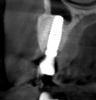

Tomographic images revealed a large tridimensional defect, with vertical and horizontal loss of bone extending to the apical third of teeth Nos. 6 and 8. Additionally, a buccal bone dehiscence was evident on tooth No. 5, and thin labial plates secondary to the orthodontic movement were present in several areas (Figure 3 and Figure 4).

Fig 3. Tomographic images revealed a tridimensional defect extending to the apical third of teeth Nos. 6 and 8, a buccal bone dehiscence on tooth No. 5, and associated thin labial plates.

Figure 3

Fig 4. Tomographic images revealed a tridimensional defect extending to the apical third of teeth Nos. 6 and 8, a buccal bone dehiscence on tooth No. 5, and associated thin labial plates.

Figure 4